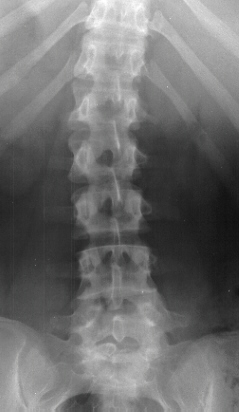

Radiological Evaluation

- plain x-rays normal, with mild spinal curve

Radiographic Findings

- mild nonstructural scoliosis

- loss of lumbar lordosis

- structural abnormality-30%